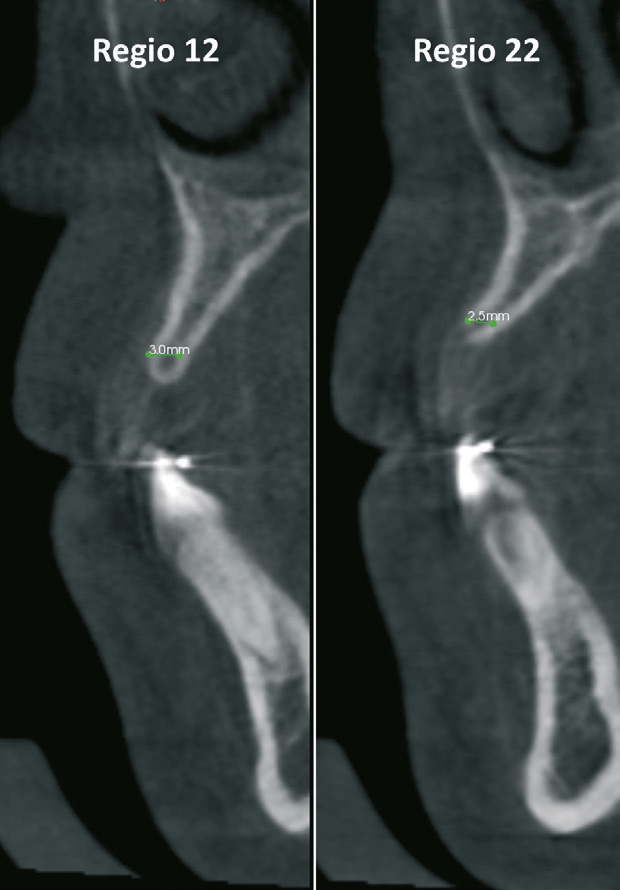

Eine 17-jährige Patientin wurde an unsere Praxis mit dem Wunsch nach einer festsitzenden implantatprothetischen Versorgung der lateralen Schneidezähne 12 und 22 überwiesen. Nach entsprechender Aufklärung und intensiver Beratung wurde zunächst ein DVT erstellt, um das genaue Ausmaß der dreidimensionalen Knochenresorption in regio der fehlenden lateralen Schneidezähne regio 12 und 22 beurteilen zu können. Die röntgenlogische Auswertung ergab eine hochgradige horizontale Alveolarfortsatzbreite von knapp 3 mm in regio 12 respektive von knapp 2,5 mm in regio 22 mit stark ausgeprägter konkaver Kontur der bukkalen Lamelle (Abb. 1). Allein das klinische Bild (Abb. 2 und 3) zeigte eine ausgeprägte horizontale Alveolarfortsatzatrophie in regio 12 und 22 mit ausgeprägten Konkavitäten in der bukkalen Lamelle.